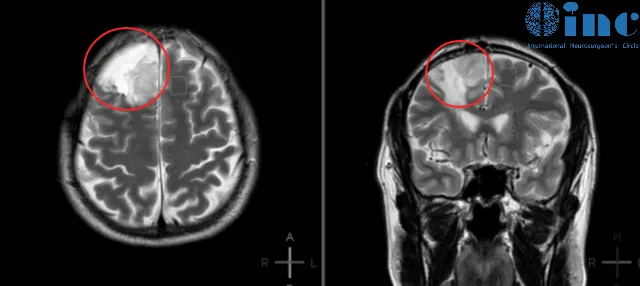

人到中年处于事业上升期的顾先生对于身体健康问题十分重视。2014年,顾先生因轻微面瘫查出——右额叶皮层区见椭圆形肿块影大小约4.9cmx3.9cmx6.8cm,提示右侧额叶少突胶质细胞瘤可能。

距离检查出右侧额叶胶质瘤仅不到一个月,顾先生就在当地医院完成了开颅手术。术后病理显示:右额少突胶质细胞瘤,WHO II级。术后顾先生每月复用替莫唑胺、丙戊酸钠片;共服用6个月,顾先生也以为自己就这样轻松摆脱了脑肿瘤。然而距离手术仅过去四年,2018年复查核磁提示复发可能。

原本以为如此简单的脑肿瘤,肯定能全切不复发了,但是看到核磁片子上的阴影,顾先生陷入了怀疑,意识到自己之前可能过于轻视这个看起来“简单”的肿瘤了。再简单的肿瘤想要100%完全切除都会变得不再“简单”。